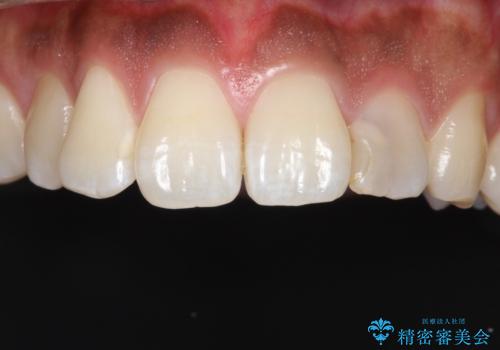

- 「前歯の歯の色が気になる」を主訴に来院された患者さんです。歯の大部分がプラスチックの材料で治療されていました。そこが劣化し変色していたためオールセラミッククラウンで治療を行いました。前歯の色を全体的に白くするために当院でオフィスホワイトニングも行いました。

左上2番の大部分がプラスチックの材料で治療されていました。そのプラスチックの材料が劣化して変色し虫歯になっている状態でした。なので古いプラスチックの材料を全て除去し、その下の虫歯を取った後、オールセラミッククラウンで治療を行いました。オールセラミッククラウンを装着する前に当院にてホワイトニングを行いました。